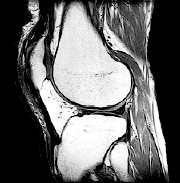

• MRI. This detailed imaging test can show bone, cartilage, ligament, or muscle problems, without using X-rays.

MRI scan of the knee.

Imaging tests such as an MRI scan may help your healthcare provider find the cause of your knee problem.